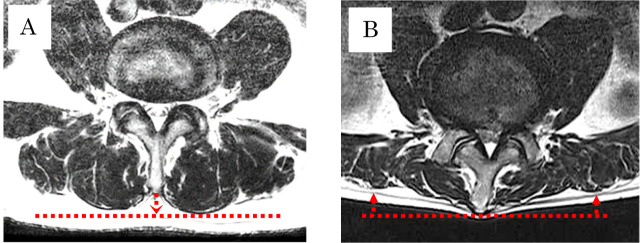

Methods: This study included 177 patients with preoperative LSS, of whom 16 had OVCFs and 161 did not. Lumbar lordosis angle, fat infiltration, and paraspinal muscle atrophy were evaluated in these patients. Information on patient characteristics such as smoking, diabetes, hemodialysis, steroid use, American Society of Anesthesiologists score, and bladder or bowel dysfunction were obtained from medical records. Logistic regression analysis was conducted to identify factors independently associated with OVCF.

Results: Patients in the OVCF group were significantly older (P=0.006) than those without fractures, and a higher proportion of the OVCF group showed muscle atrophy (P=0.034). Significant variables and those with moderate effect sizes were included in the logistic regression analysis. Muscle atrophy (P=0.028) was independently associated with OVCF.